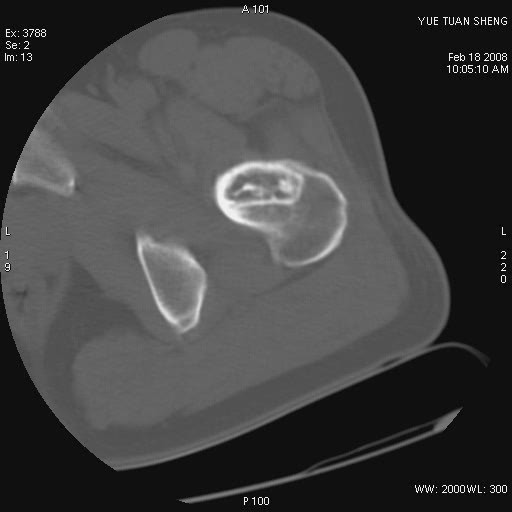

患者,男,56岁,左髋部疼痛1个月,x线:左股骨头高密度影,性质待定,右侧正常。左髋ct如图

左股骨颈区椭圆形磨玻璃样影,边缘明显硬化环环绕,其内见斑点状类钙化高密度影考虑 良性骨病-----骨纤,骨化性纤维瘤,内生软骨瘤。